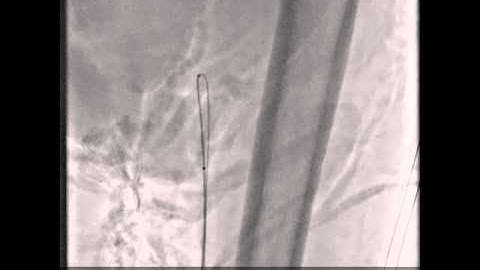

CTO case : from antegrade to retrograde, twin pass and rotablator carries a solution